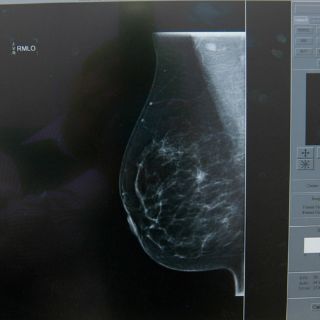

Proteger los huesos evitaría metástasis del cáncer de mama

Alrededor del 85 por ciento de los cánceres de mama que se expanden por el cuerpo terminan en los huesos